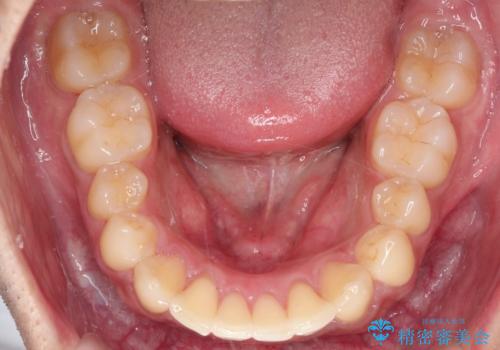

- 歯並びの凸凹を主訴に来院されました。

スペースが必要なため、抜歯を行なって治療を行いました。

奥歯の捻れが強く治療期間がかかりましたが、綺麗な仕上がりに満足していただきました。